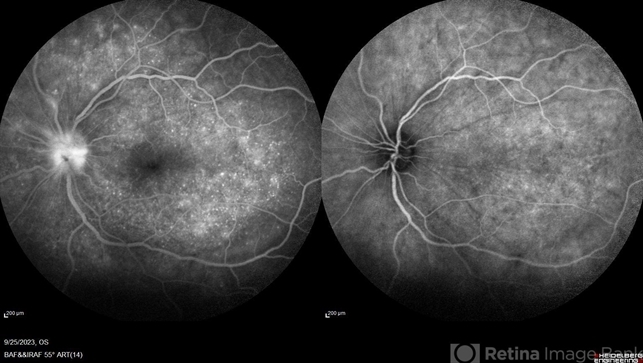

- Late frame of FA+ICG of LE of a 41 year old female showing disc leakage with hyperfluorescence suggestive of leakage with hypofluoroscence on FA and ICG in a case of VKH.